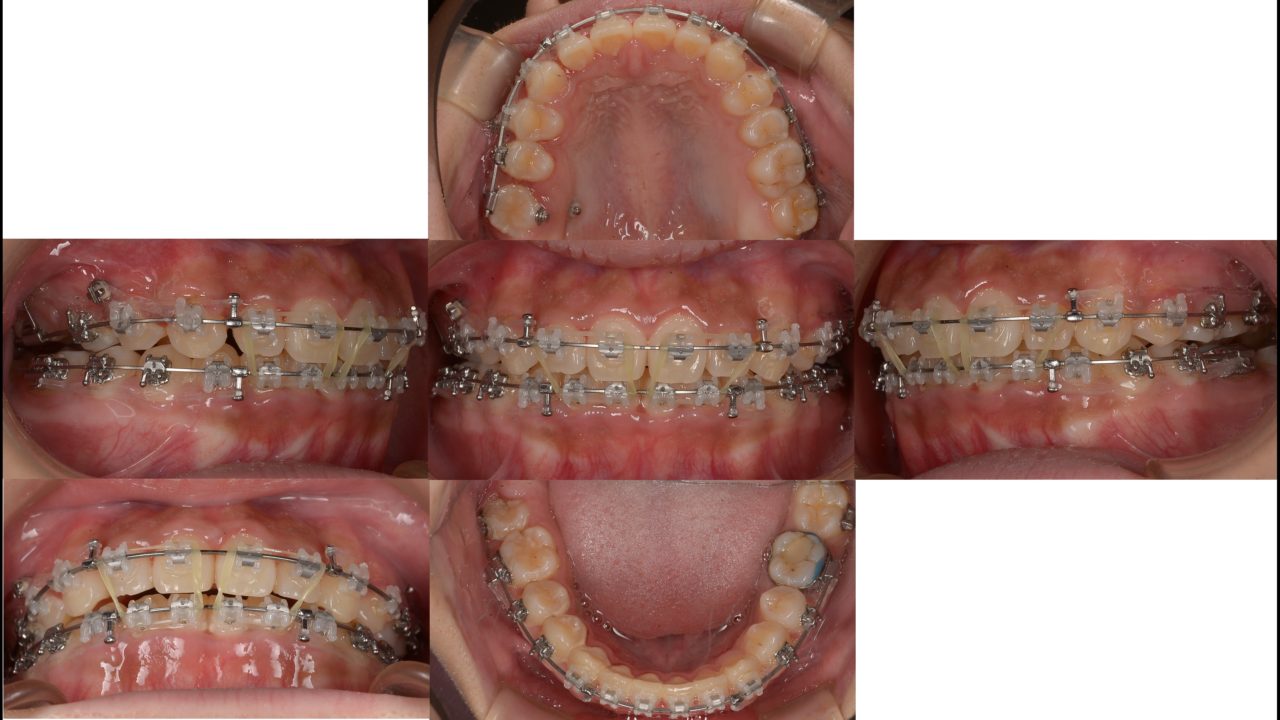

2021.10.11 治療開始9か月